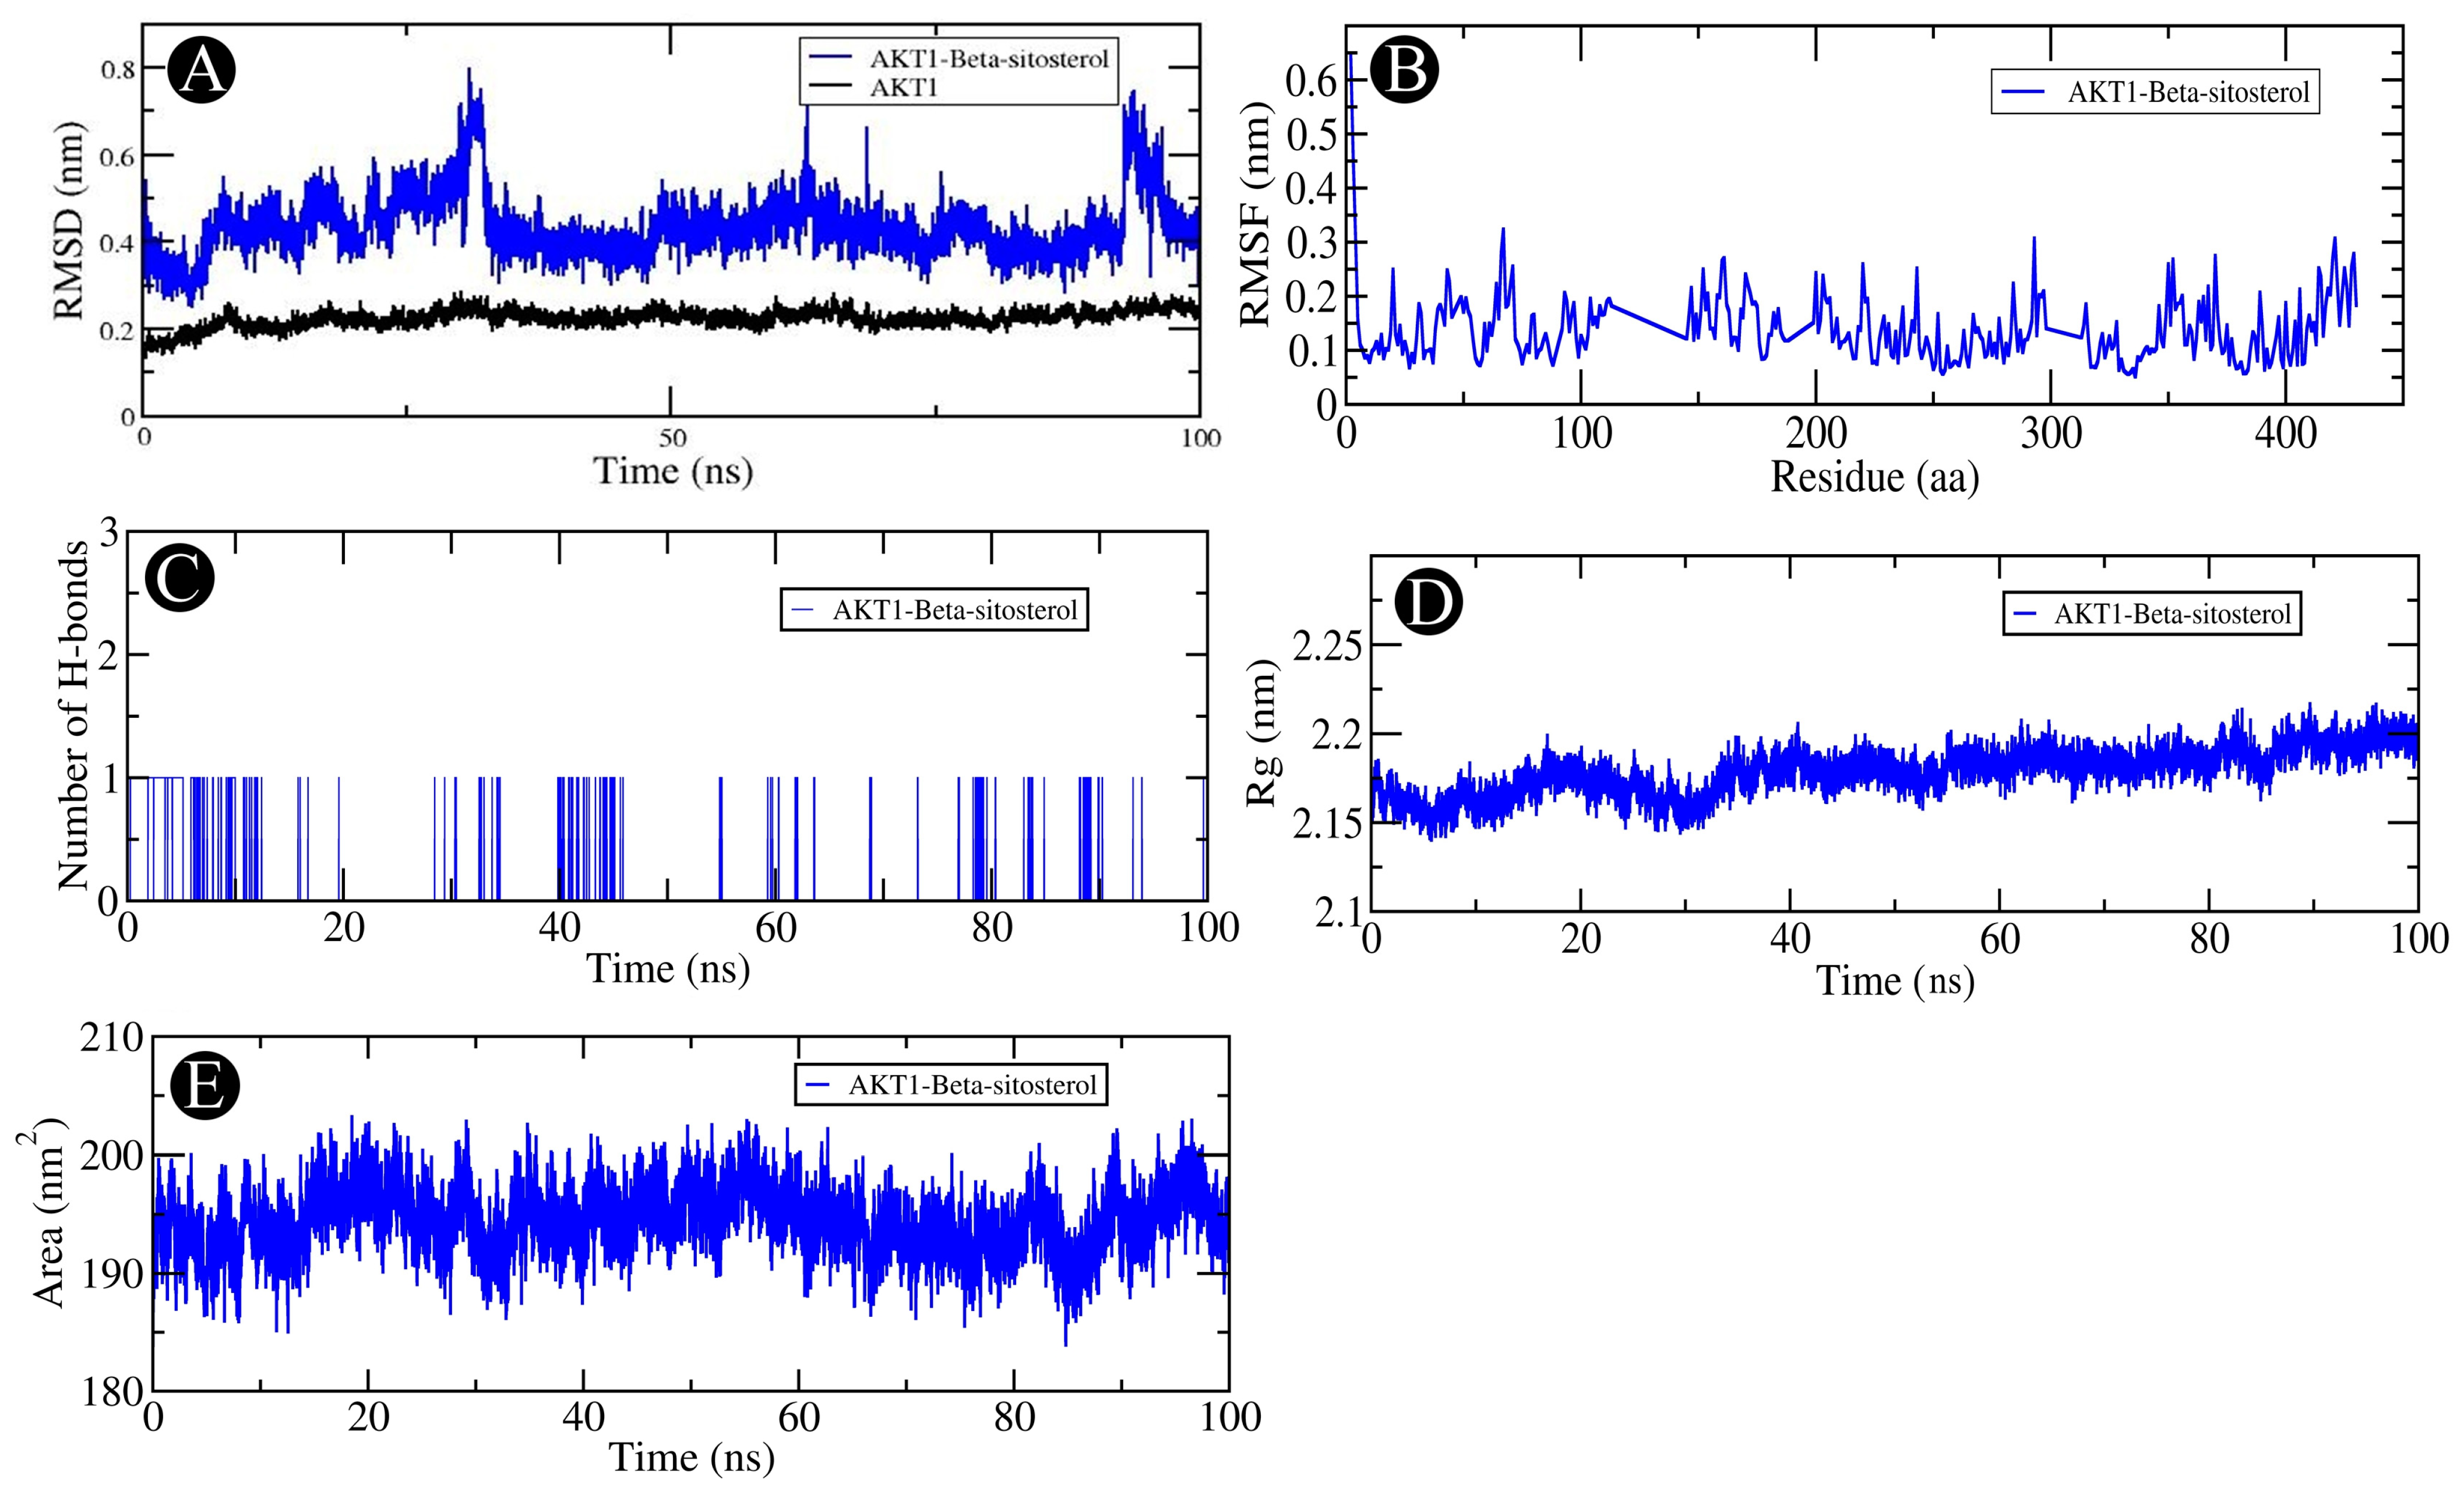

2.6. MD Simulation Analysis